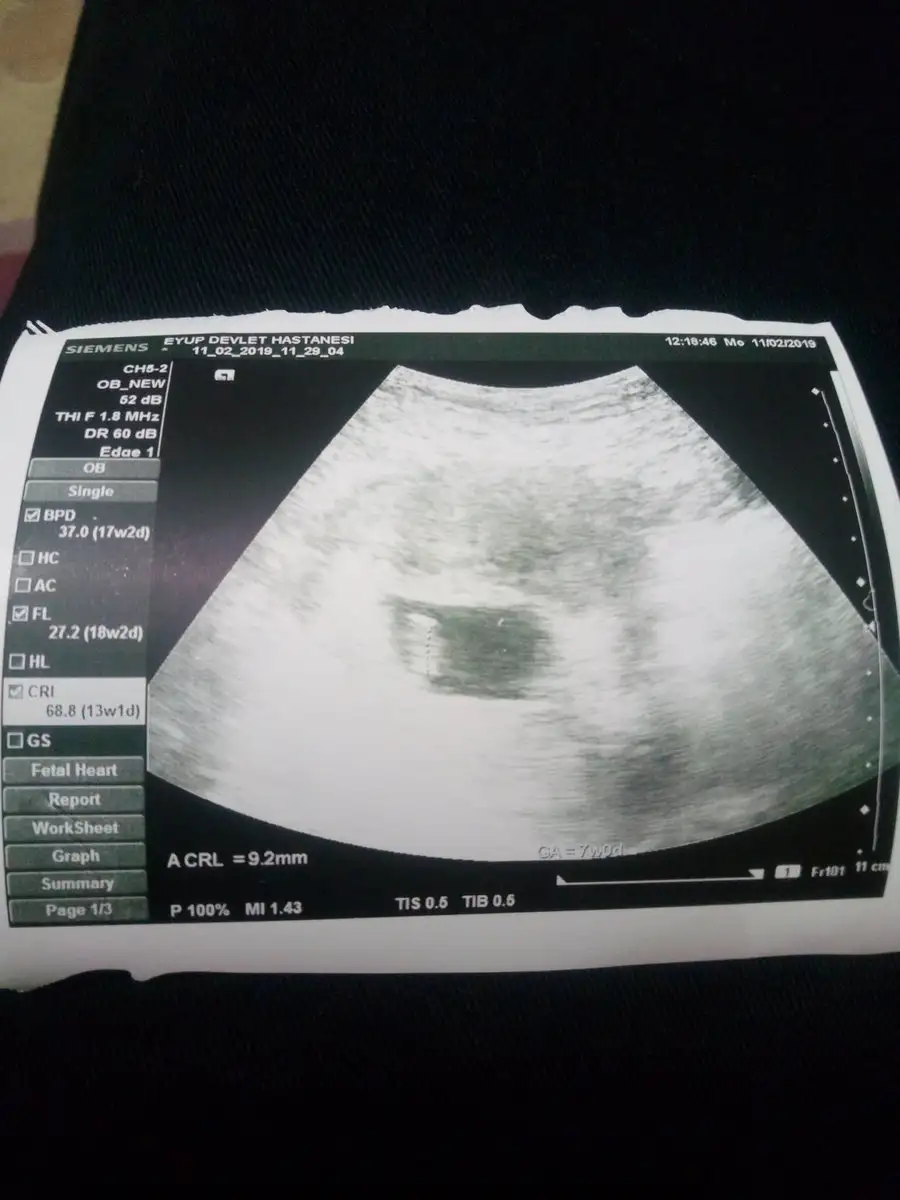

Kızlar 6-7 haftalık ultrason görüntülerine göre yorum yapıyorum, 11 haftalıktan itibaren de nub yorumu yapıyorum. Tahmin isteyen yazın bana, sayfam var zaten bu konuya ait çoğu tutuyor